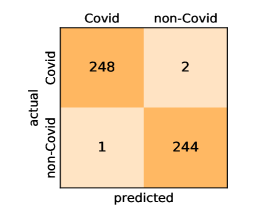

Here, we present and discuss the obtained results for detecting COVID-19 on the considered CT image datasets with different deep networks. We report the quantitative results along with the confusion matrices for every single architecture of the adopted networks.

On the SARS-CoV-2 CT dataset, ResNet101 achieves the best overall performance with respect to almost all evaluation metrics, with an average accuracy and F1-score of and , respectively. The model also achieves an average sensitivity rate of indicating that, on average, only two COVID-19 images are falsely predicted as negatives. It is also powerful enough to correctly identify all Non-COVID-19 cases with only one false positive resulting a specificity rate of . The highest sensitivity score of is achieved by the InceptionV3 model, where only one COVID-19 image is falsely predicted as negative on average. The SqueezeNet model obtains the lowest performance with respect to all evaluation metrics with a fairly acceptable average accuracy and sensitivity scores of and , respectively. Also the ShuffleNet architecture obtains satisfactory performance with approximately improvements on average for all metrics compared with SqueezeNet. Although the results obtained by these models are inferior compared with the rest of models, but they are more efficient. This matches their main objective of reducing the computational costs rather than improving their visual recognition abilities. The rest of models achieve competitive performance and very promising results with slight performance differences. Comparing the different variants of ResNet and DenseNet, we can see that the deeper variants from each architecture yield a slightly better performance. The deeper ResNet101 and ResNeXt101 show a marginal gain in performance compared with their shallower counterparts. The details about class-wise results for each model are summarized in the confusion matrices in Figure 9.

It is worthy mentioning that on the SARS-CoV-2 CT dataset the inter-fold variations are minimal and usually below one percent, showing the robustness of our fine-tuning strategy. For some of the architectures like the DenseNet variants we observe a larger confidence interval than their actual differences in recognition performance. This means that the DenseNets and the deeper ResNet variants share a very similar performance and are almost indistinguishable from each other. Overall, the obtained results by our models are better than the recently published ones even when using the same network architectures. We attribute this to the better optimization and transferability of the learned features when applying our fine-tuning strategy.